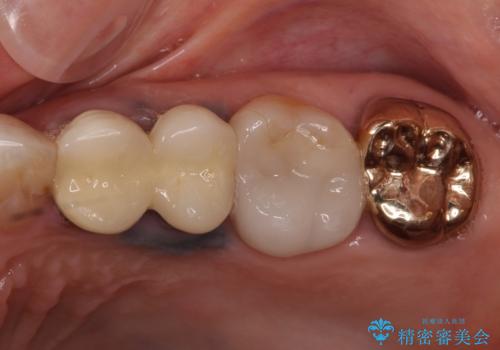

金属の縁が見えてしまったクラウン オールセラミッククラウンで審美的に